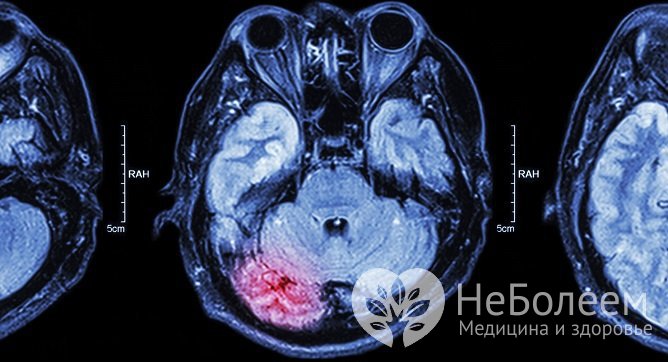

Прогноз при поражении разных участков мозга

При поражении ствола головного мозга летальный исход в 65% случаев наступает в первые два дня от начала болезни. В результате своевременной госпитализации и адекватной терапии прогноз несколько улучшается. В первые несколько месяцев после развития нарушений в области ствола мозга врачи дают положительный прогноз восстановления нарушенной двигательной функции, в дальнейшем темп замедляется. В некоторых случаях двигательная функция восстанавливается частично в течение года с начала развития заболевания.

При ишемическом инсульте мозжечка в начальном периоде велика вероятность развития выраженного отека зоны поражения. Если в течение первого дня больному не была оказана медицинская помощь, отек начинает сдавливать стволовые структуры, что может привести к необратимым повреждениям ствола головного мозга, острой окклюзионной гидроцефалии, коме и летальному исходу. Вовремя выполненное хирургическое вмешательство и медикаментозное лечение позволяет минимизировать последствия и снизить смертность при ишемическом инсульте мозжечка до 30%.

При инсульте затылочной зоны мозга происходит расстройство двигательных функций на стороне тела, противоположной пораженному полушарию. Если поражено левое полушарие, человек перестает видеть, что находится в правой части поля зрения, и наоборот. В большинстве случае после адекватного лечения прогноз положительный, зрение восстанавливается в течение полугода после начала болезни. Иногда человек навсегда утрачивает способность идентифицировать редко наблюдаемые предметы и узнавать малознакомых людей.

Прогноз для жизни после комы осторожный. Кома развивается при обширном поражении тканей мозга. Обширный инсульт проявляется сильными головными болями, потерей зрения, речи, чувствительности лица, поражением центра терморегуляции, дыхательного центра, тяжелыми расстройствами функции сердечно-сосудистой системы. При этих нарушениях риск летального исхода очень высок. Шанс частичного восстановления функций – менее 15%.